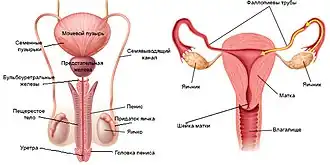

Фалло́пиевы тру́бы (также ма́точные трубы) — яйцевод у млекопитающих[1], парный трубчатый орган, соединяющий полость матки с брюшной полостью. Названы по имени итальянского анатома XVI века Габриеле Фаллопия, впервые описавшего их.

Строение

Яичниковый конец маточной трубы (extremitas ovarica) имеет воронкообразное расширение (infundibulum tubae uterinae). Края этой воронки маточной трубы имеют многочисленные отростки неправильной формы и называются бахромкой трубы (fimbria tubae). Часть бахромки соединяющуюся с передним краем яичника называют бахромкой яичника (fimbria ovarica). Маточный конец трубы (extremitas uterina) соединяется маточным отверстием (ostium uterinum tubae) с рогом матки. Между двумя концами трубы располагаются короткий узкий и относительно прямой перешеек (isthmus tuba uterina), и сильно извитая расширенная ампула маточной трубы, составляющая около половины (иногда до двух третей) длины трубы.

Стенка маточной трубы состоит из трех оболочек: слизистой, мышечной и серозной. Слизистая оболочка имеет многочисленные продольные складки (plicae tubariae). В эпителии слизистой оболочки имеются секреторные и реснитчатые клетки. Секреторные клетки вырабатывают необходимые для питания яйцеклетки вещества. Мышечная оболочка включает в себя циркулярные и продольные пучки гладких мышечных клеток. Перистальтические сокращения мышечной оболочки и мерцание ресничек эпителия обеспечивает продвижение яйцеклетки по яйцеводу в направлении к рогу матки. Внешняя серозная оболочка маточной трубы продолжающется в брыжейку маточной трубы (mesosalpinx) формирует широкую маточную связку (lig. latum uteri).